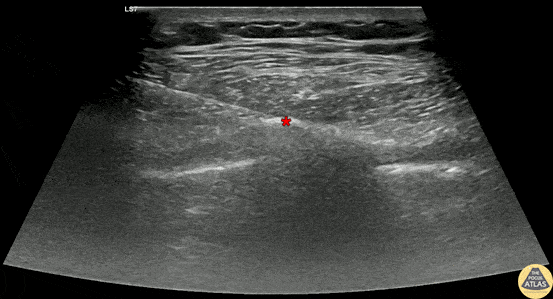

60s M presented with unilateral chest pain and a rash, and was ultimately diagnosed with a flare of herpes zoster. To aid in pain control, a serratus anterior plane block was performed. The block is shown here, with the needle advanced using in-plane guidance to the fascial plane (*) between the deeper intercostal muscles and more superficial serratus anterior muscle, where anesthetic was injected. The patient had improvement in their pain and was able to be discharged. Dr. Henrik Galust, PGY4 Denver Health Residency in Emergency Medicine